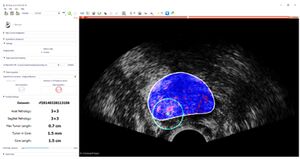

Toward a Real-time System for Temporal Enhanced Ultrasound-guided Prostate Biopsy

Publication: Int J Comput Assist Radiol Surg. 2018 Aug;13(8):1201-9. PMID: 29589258 | PDF Authors: Azizi S, Van Woudenberg N, Sojoudi S, Li M, Xu S, Abu Anas EM, Yan P, Tahmasebi A, Kwak JT, Turkbey B, Choyke P, Pinto P, Wood B, Mousavi P, Abolmaesumi P. Institution: The University of British Columbia, Vancouver, BC, Canada. Abstract: PURPOSE: We have previously proposed temporal enhanced ultrasound (TeUS) as a new paradigm for tissue characterization. TeUS is based on analyzing a sequence of ultrasound data with deep learning and has been demonstrated to be successful for detection of cancer in ultrasound-guided prostate biopsy. Our aim is to enable the dissemination of this technology to the community for large-scale clinical validation. METHODS: In this paper, we present a unified software framework demonstrating near-real-time analysis of ultrasound data stream using a deep learning solution. The system integrates ultrasound imaging hardware, visualization and a deep learning back-end to build an accessible, flexible and robust platform. A client-server approach is used in order to run computationally expensive algorithms in parallel. We demonstrate the efficacy of the framework using two applications as case studies. First, we show that prostate cancer detection using near-real-time analysis of RF and B-mode TeUS data and deep learning is feasible. Second, we present real-time segmentation of ultrasound prostate data using an integrated deep learning solution. RESULTS: The system is evaluated for cancer detection accuracy on ultrasound data obtained from a large clinical study with 255 biopsy cores from 157 subjects. It is further assessed with an independent dataset with 21 biopsy targets from six subjects. In the first study, we achieve area under the curve, sensitivity, specificity and accuracy of 0.94, 0.77, 0.94 and 0.92, respectively, for the detection of prostate cancer. In the second study, we achieve an AUC of 0.85. CONCLUSION: Our results suggest that TeUS-guided biopsy can be potentially effective for the detection of prostate cancer. |

Guidance interface implemented as part of a 3D Slicer module: cancer likelihood map is overlaid on B-mode ultrasound images. Red indicates predicted labels as cancer, and blue indicates predicted benign regions. The boundary of the segmented prostate is shown with white, and the green circle is centered around the target location which is shown in green dot. |